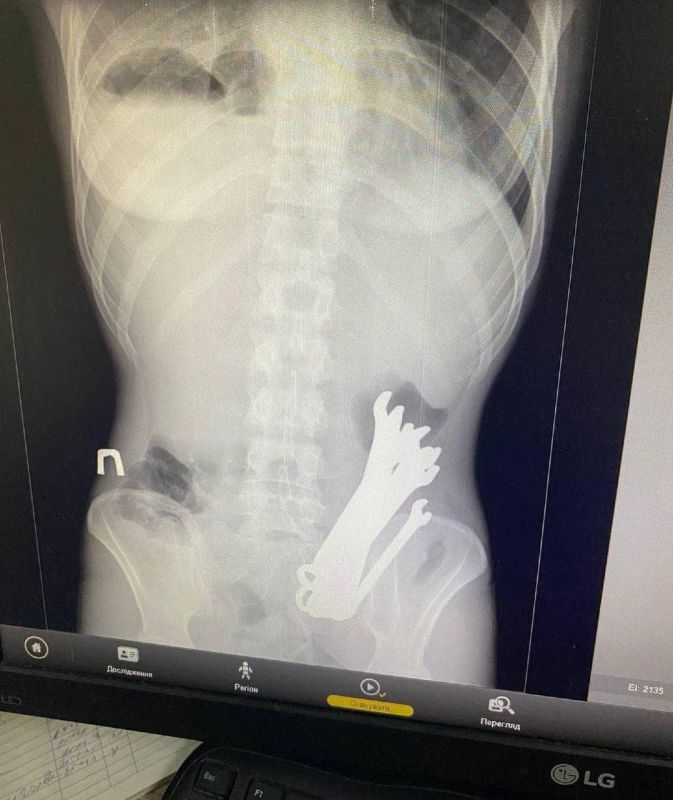

Украинец проглотил шесть гаечных ключей чтобы «вылечить запор»Об этом рассказали в Черкасской областной больнице.Необычный пациент поступил к ним сегодня — мужчина пожаловался, что ранее проглоченные инструменты не выходят.Доставать их...